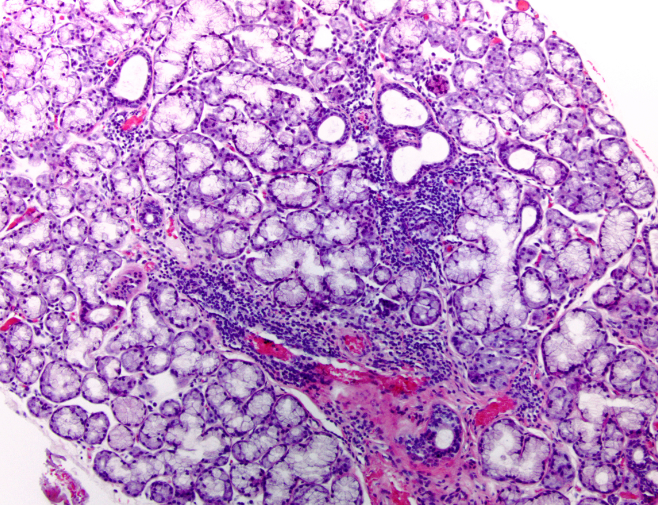

Histopathology

Histopathology is the diagnosis and study of diseases of the tissues, and involves examining

tissues and/or cells under a microscope. Histopathologists are responsible for making tissue

diagnoses and helping clinicians manage a patient’s care. Histopathologists are doctors who work

closely with other clinical specialties. They can reach a diagnosis by examining a small piece of tissue

from the skin, liver, kidney or other organ. This is called a biopsy. Many histopathologists specialise in